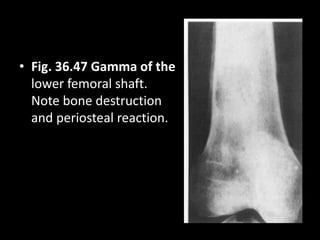

• Fig. 36.47 Gamma of the

lower femoral shaft.

Note bone destruction

and periosteal reaction.

• Fig. 36.47Gamma of the lower femoral shaft. Note bone destruction and periosteal reaction.